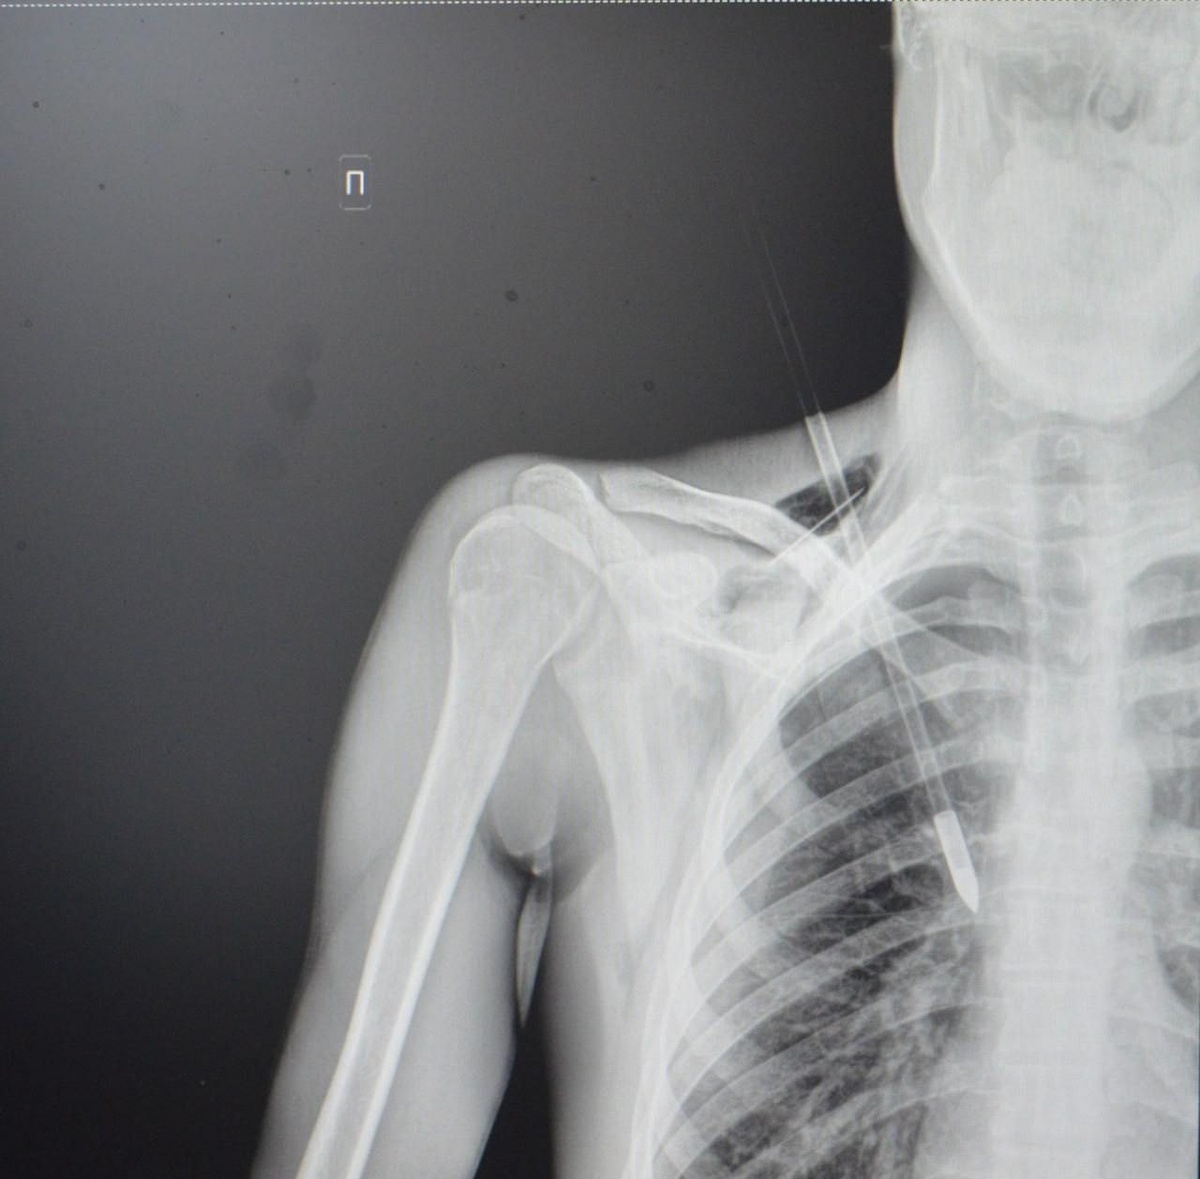

В Ступинскую больницу поступил 20-летний пациент с необычным ранением - стрелой в грудной клетке. Инцидент произошел в парке, где молодой человек со своей девушкой занимались стрельбой из спортивного лука. По его словам, стрела рикошетом от дерева попала ему прямо в грудь. «Пациенту невероятно повезло - стрела могла задеть подключичную артерию или вену, что привело бы к критическому кровотечению. Такие травмы требуют немедленного хирургического вмешательства. Мы успешно удалили инородное тело, а потом ушили поврежденное легкое и дренировали плевральную полость», - прокомментировал врач-хирург Ступинской больницы Тимур Колесников. Врачи прогнозируют благоприятный исход лечения при соблюдении всех медицинских рекомендаций. В ближайшее время его выпишут.

В Ступинскую больницу поступил 20-летний пациент с необычным ранением - стрелой в грудной клетке. Инцидент произошел в парке, где молодой человек со своей девушкой занимались стрельбой из спортивного лука. По его словам, стрела рикошетом от дерева попала ему прямо в грудь.

«Пациенту невероятно повезло - стрела могла задеть подключичную артерию или вену, что привело бы к критическому кровотечению. Такие травмы требуют немедленного хирургического вмешательства. Мы успешно удалили инородное тело, а потом ушили поврежденное легкое и дренировали плевральную полость», - прокомментировал врач-хирург Ступинской больницы Тимур Колесников.

Врачи прогнозируют благоприятный исход лечения при соблюдении всех медицинских рекомендаций. В ближайшее время его выпишут.